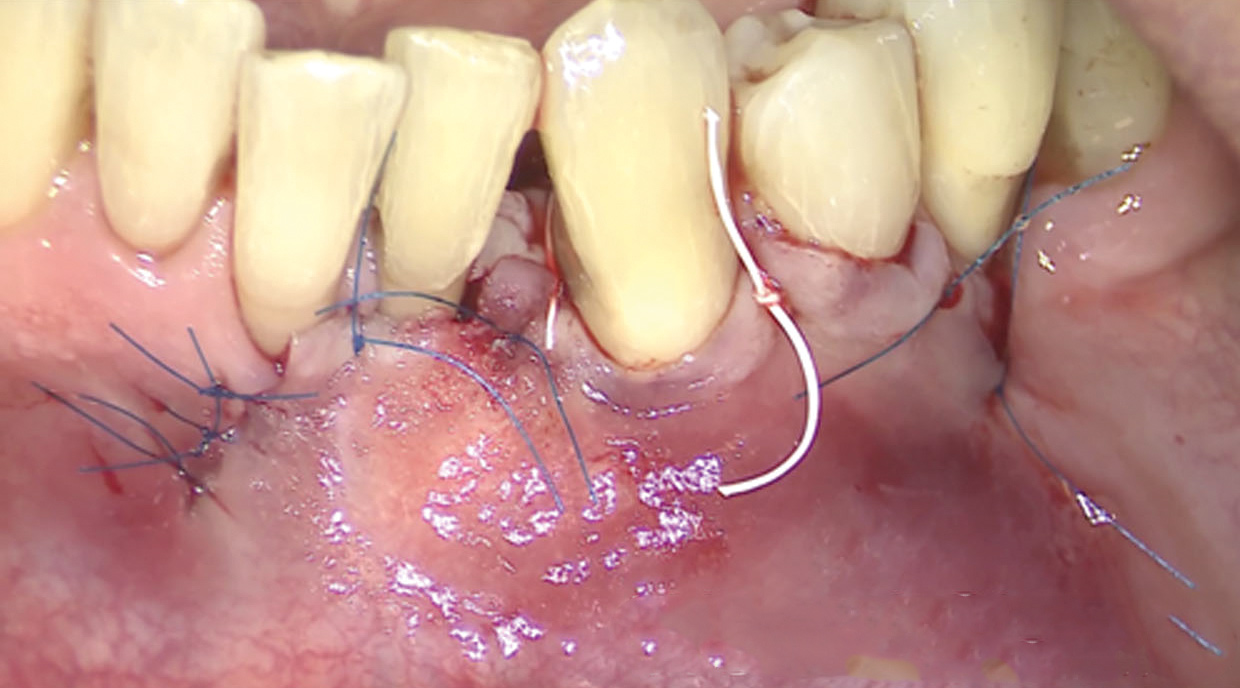

Fig 13. The scaffold was placed in the defect, where it remained for approximately 1 year. Fig 13: baseline; Fig 14: defect; Fig 15: scaffold matrix; Fig 16: scaffold placement; Fig 17: wound closure; Fig 18 through Fig 20: 2-month, 6-month, and 1-year postoperative, respectively. (Images reprinted with permission from Rasperini G, Pilipchuk SP, Flanagan CL, et al. J Dent Res. 2015;94[9 suppl]:153S-157S.)

Fig 14. The scaffold was placed in the defect, where it remained for approximately 1 year. Fig 13: baseline; Fig 14: defect; Fig 15: scaffold matrix; Fig 16: scaffold placement; Fig 17: wound closure; Fig 18 through Fig 20: 2-month, 6-month, and 1-year postoperative, respectively. (Images reprinted with permission from Rasperini G, Pilipchuk SP, Flanagan CL, et al. J Dent Res. 2015;94[9 suppl]:153S-157S.)

Fig 15. The scaffold was placed in the defect, where it remained for approximately 1 year. Fig 13: baseline; Fig 14: defect; Fig 15: scaffold matrix; Fig 16: scaffold placement; Fig 17: wound closure; Fig 18 through Fig 20: 2-month, 6-month, and 1-year postoperative, respectively. (Images reprinted with permission from Rasperini G, Pilipchuk SP, Flanagan CL, et al. J Dent Res. 2015;94[9 suppl]:153S-157S.)

Fig 16. The scaffold was placed in the defect, where it remained for approximately 1 year. Fig 13: baseline; Fig 14: defect; Fig 15: scaffold matrix; Fig 16: scaffold placement; Fig 17: wound closure; Fig 18 through Fig 20: 2-month, 6-month, and 1-year postoperative, respectively. (Images reprinted with permission from Rasperini G, Pilipchuk SP, Flanagan CL, et al. J Dent Res. 2015;94[9 suppl]:153S-157S.)

Fig 17. The scaffold was placed in the defect, where it remained for approximately 1 year. Fig 13: baseline; Fig 14: defect; Fig 15: scaffold matrix; Fig 16: scaffold placement; Fig 17: wound closure; Fig 18 through Fig 20: 2-month, 6-month, and 1-year postoperative, respectively. (Images reprinted with permission from Rasperini G, Pilipchuk SP, Flanagan CL, et al. J Dent Res. 2015;94[9 suppl]:153S-157S.)